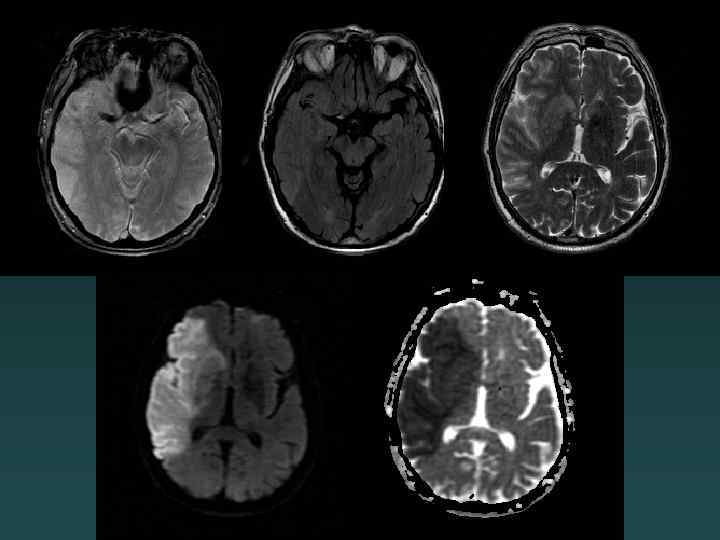

Diffusion-MRI: Acute Infarct

MRI: Diffuse Axonal Injury